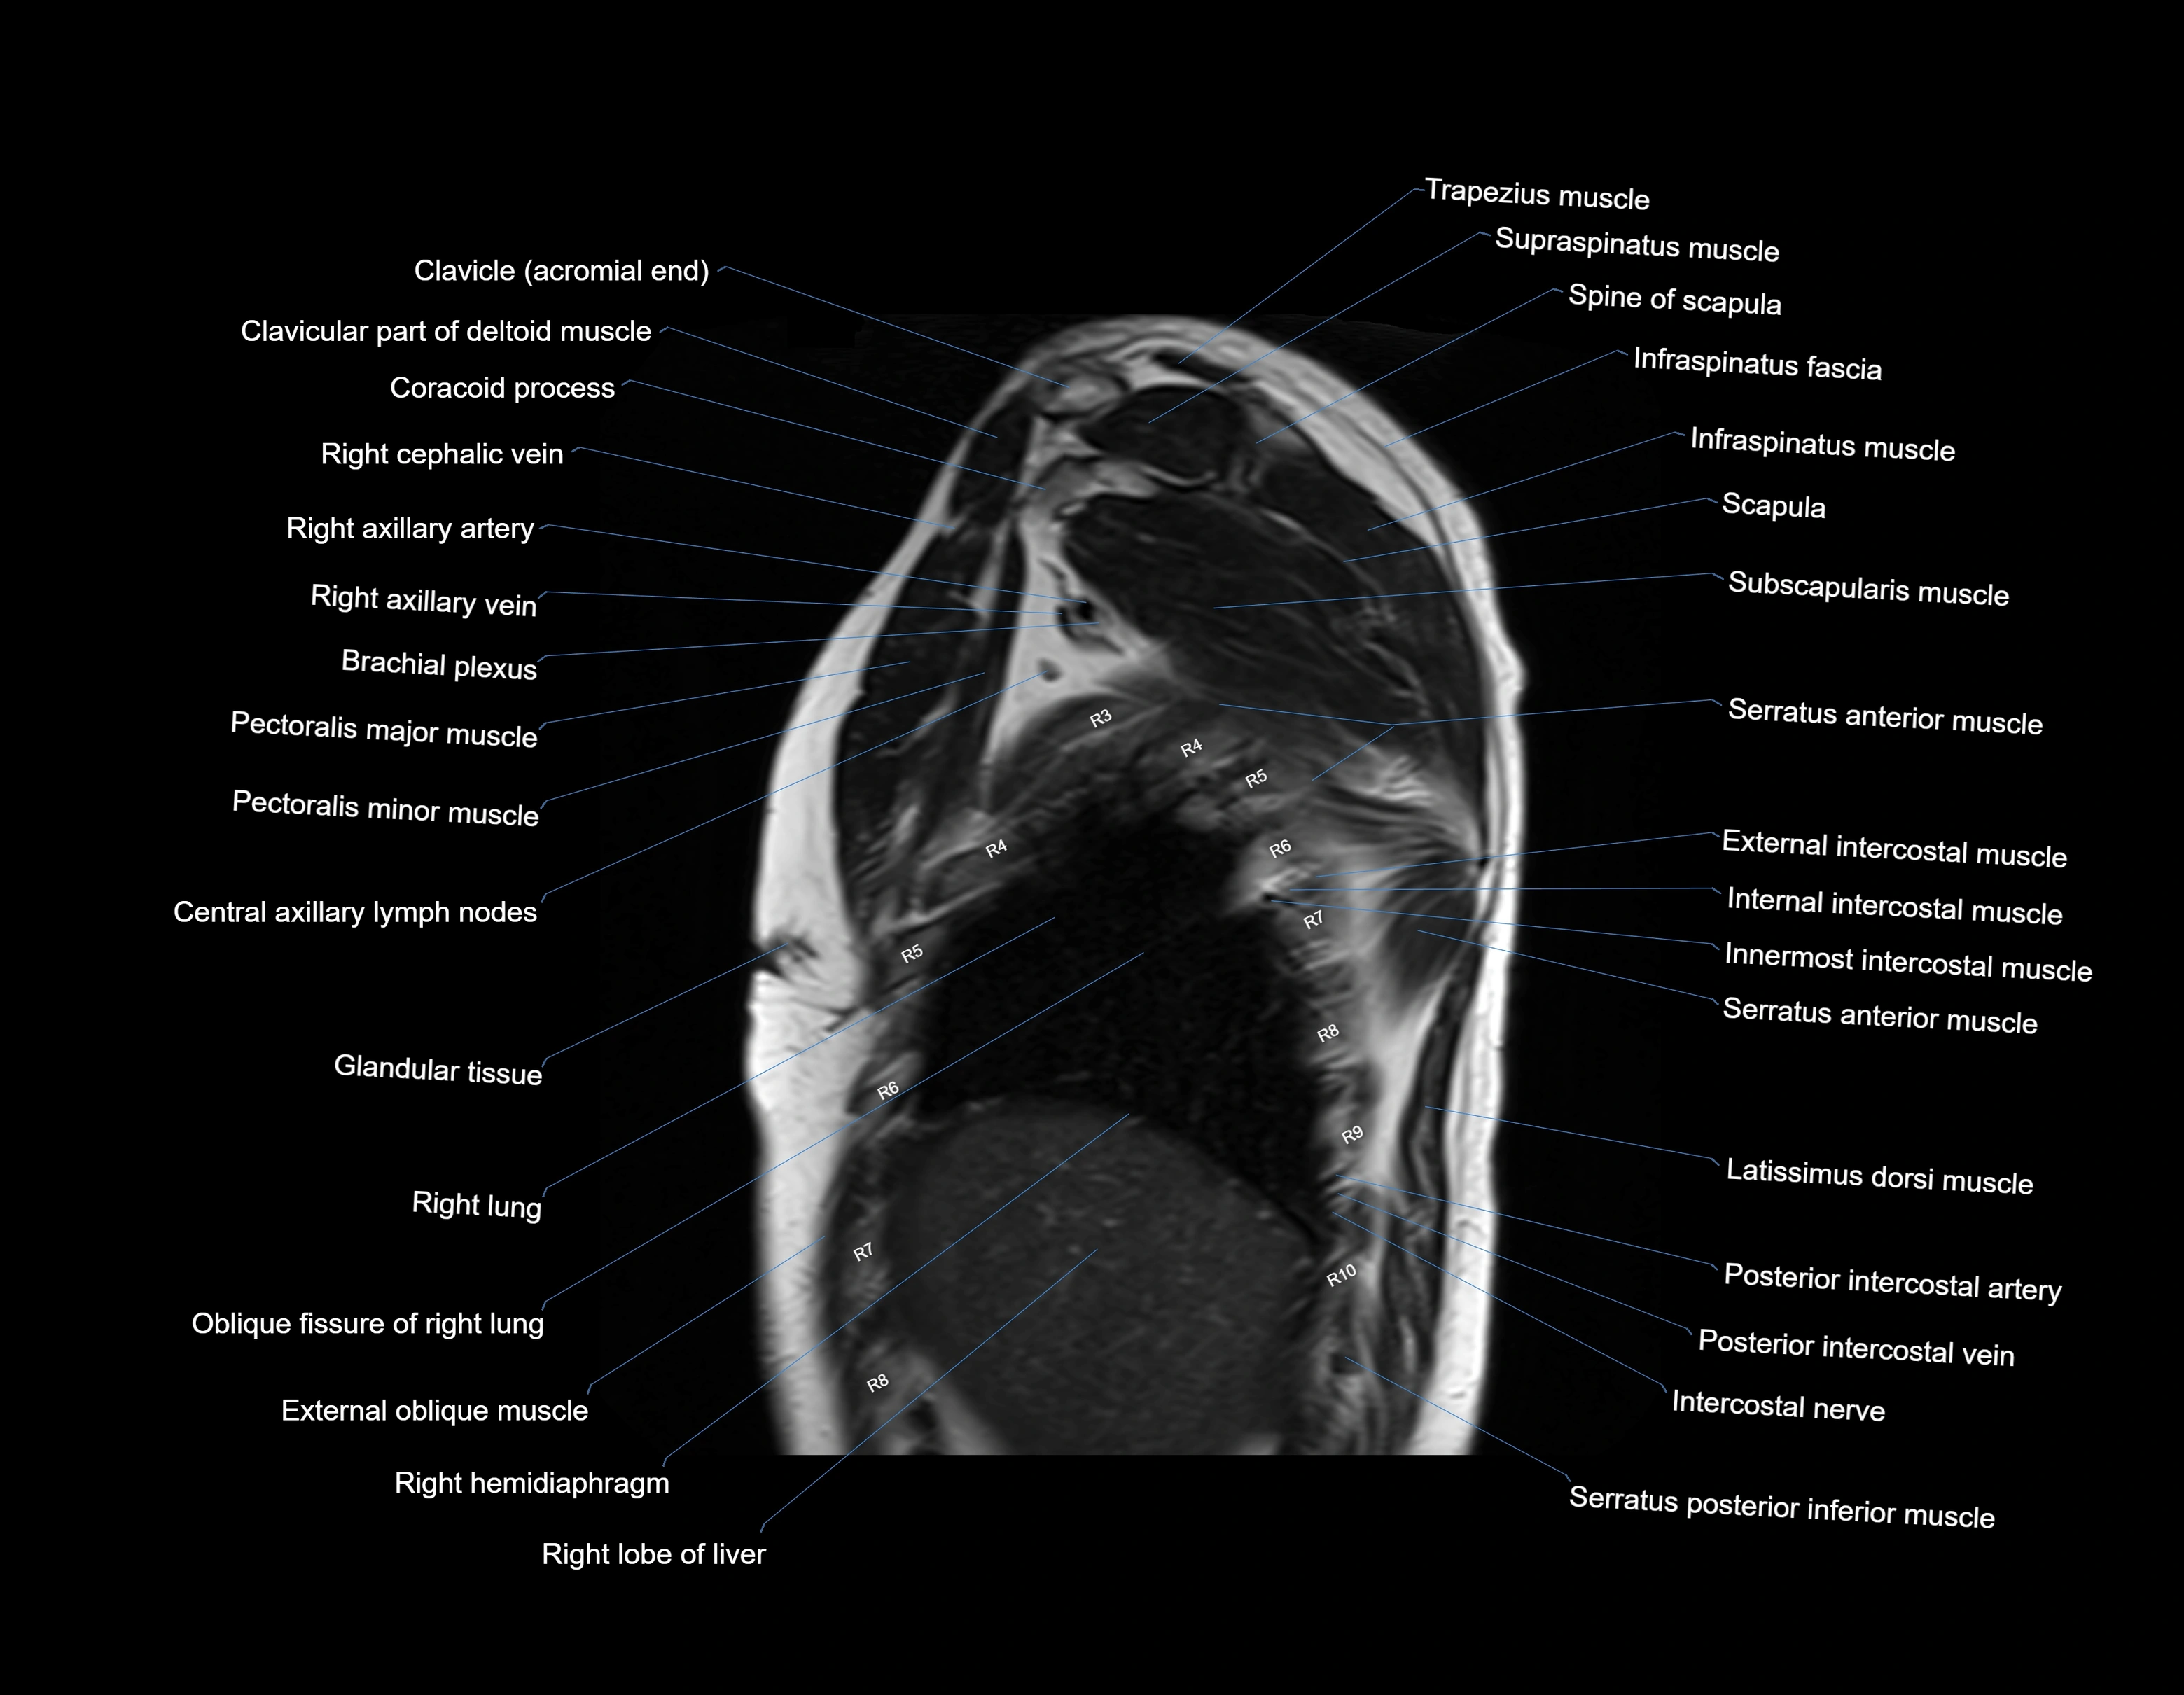

- Brachial plexus

- Central axillary lymph nodes

- Cephalic vein

- Infraspinatus muscle

- Pectoralis major muscle

- Pectoralis minor muscle

- Serratus anterior muscle

- Serratus posterior inferior muscle